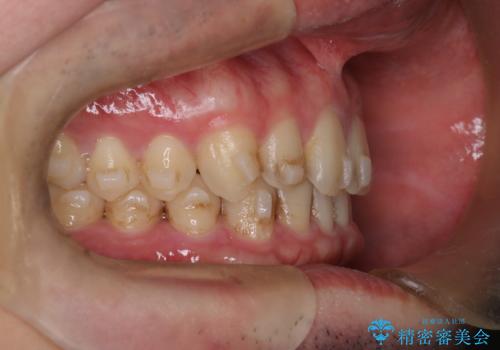

【インビザライン】前歯の隙間を治したい。

- 前歯の隙間を主訴に来院されました。

インビザラインにて治療しました。

ディープバイトも改善でき患者さんも満足されていました。

前歯の隙間だけを閉じる治療を行うだけでは、噛み合わせが悪くなるためディープバイトも改善が必要です。